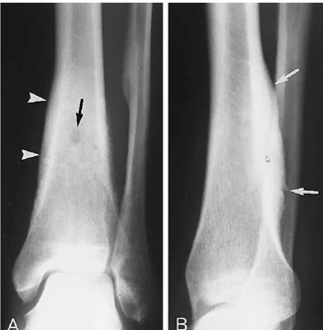

Kyste anévrismal osseux :

- ++ fémur, tibia et fibula (80%)

- Bénin mais ++ risque de fx patho car le cortex est aminci et l’os est « expanded